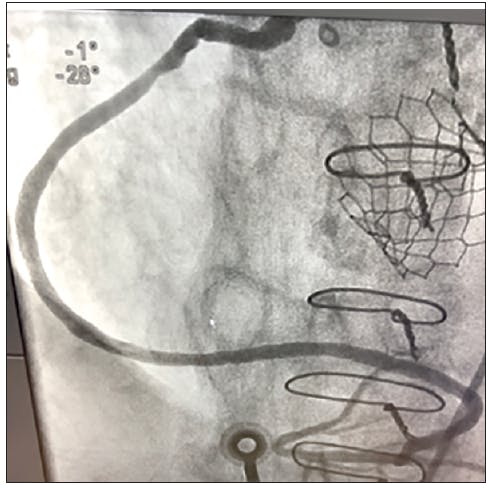

A 92-year-old man with a history of coronary artery disease (treated previously with coronary artery bypass graft) and severe aortic stenosis (treated previously with transcatheter aortic valve replacement) presented to the ED with chest pain. The patient had reported intermittent chest discomfort for 3 days, with some improvement with his daily medications. The pain became more intense and constant, so he presented to the ED. The patient was brought to the catheterization laboratory for angiography that showed stagnant flow through the saphenous vein graft (SVG; Figure 1).

INTERVENTION

We decided to start with mechanical aspiration using CAT RX and Penumbra ENGINE to extract the thrombus. After just one pass with CAT RX and 20 seconds of aspiration, the thrombus was removed. Angiography was performed and confirmed complete thrombus removal and flow restoration through the SVG. We directly stented with a 3.5- X 38-mm Synergy DES and postdilated with a 4- X 20-mm noncompliant balloon. The final angiographic outcome revealed complete revascularization and TIMI 3 flow (Figure 2).

DISCUSSION

SVG occlusions can be challenging to resolve using traditional treatment modalities. Relying on a different mechanism of action, power aspiration with CAT RX and Penumbra ENGINE was able to extract the thrombus intact; thus restoring flow through the graft. CAT RX has allowed us to rethink how we approach these occluded SVGs.